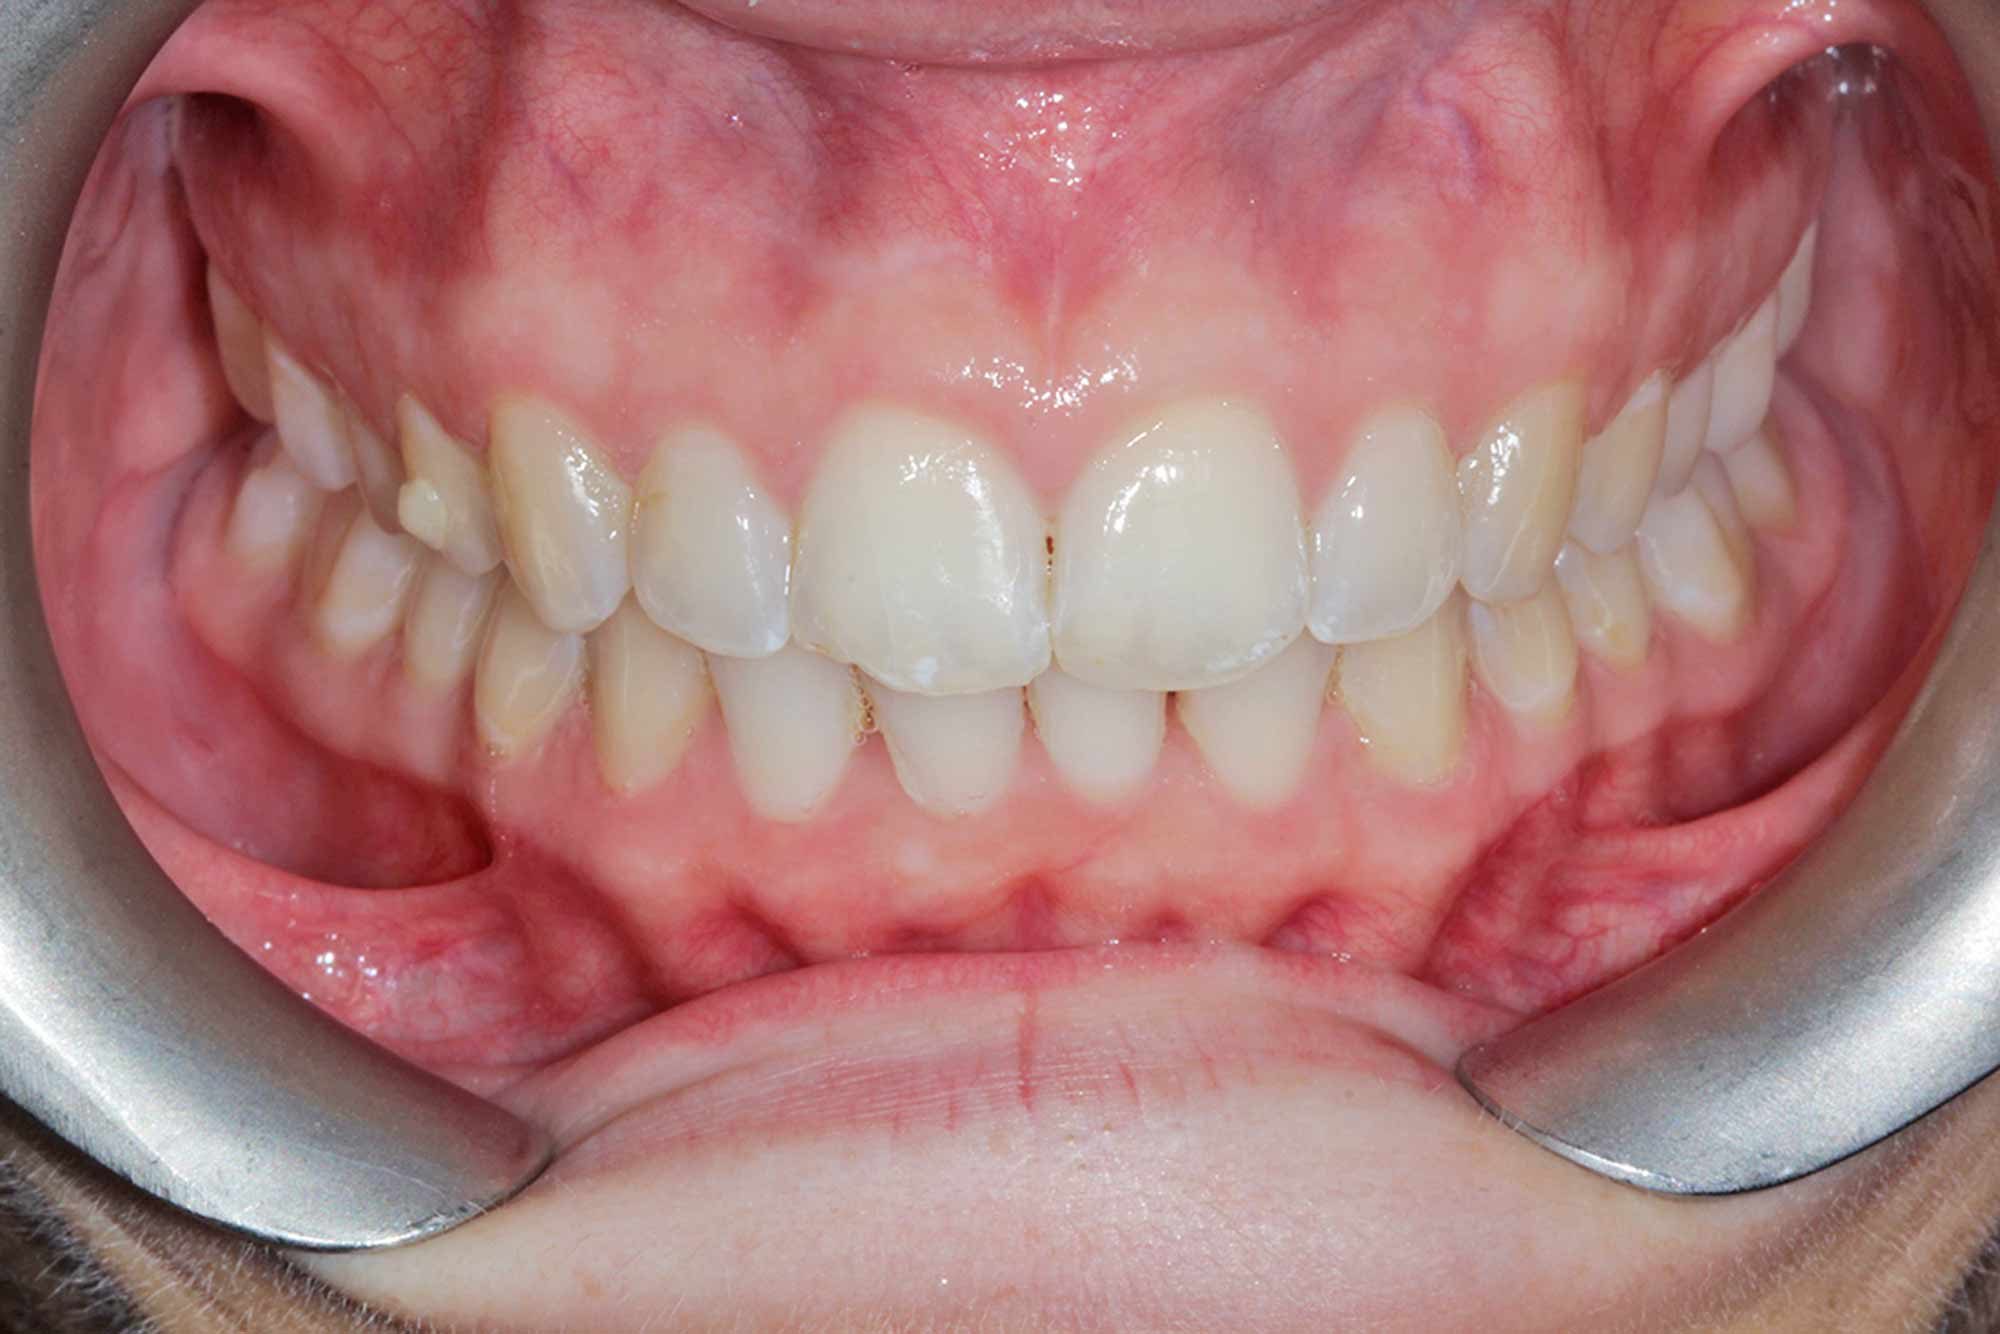

We ultimately achieved a BL1 result, which well exceeded the patient’s expectation.

I achieved this with six weeks of night time whitening, which is fast becoming the norm for those desiring much whiter finishes.

Once the tooth positioning and colour were both at an exemplary stage, it was time to frame the result with composite direct edge bonding. This has been made much easier due to all the other factors. Our restorative material of choice for this case was Venus Pearl shade BL. This matched the patient’s newly whitened teeth perfectly.

The other factors had been carried out to such a high level, that the bonding stage was very straightforward and fairly easy to conduct. Using the right tools to blend the margins in and polish them to give this case even more longevity in the long run. The key to these cases is anatomy. Match the anatomy and proportions, and it will blend beautifully.